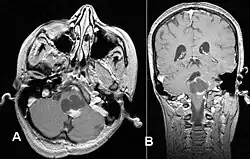

Stereotactic MRI brain scan showing a recurrent postoperative brain stem cystic pilocytic astrocytoma.

Pilocytic astrocytoma in the hypothalamic region

T1-weighted coronal MRI image postcontrast showing heterogeneous contrast enhancement within the presumed tectal plate glioma